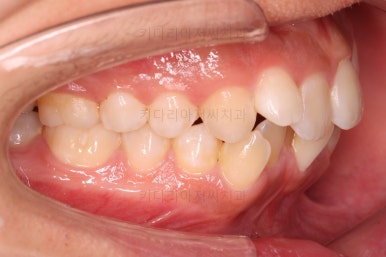

초진 시 입안의 모습입니다.

앞니가 많이 삐뚤고, 송곳니가 부각되어 덧니처럼 보이네요.